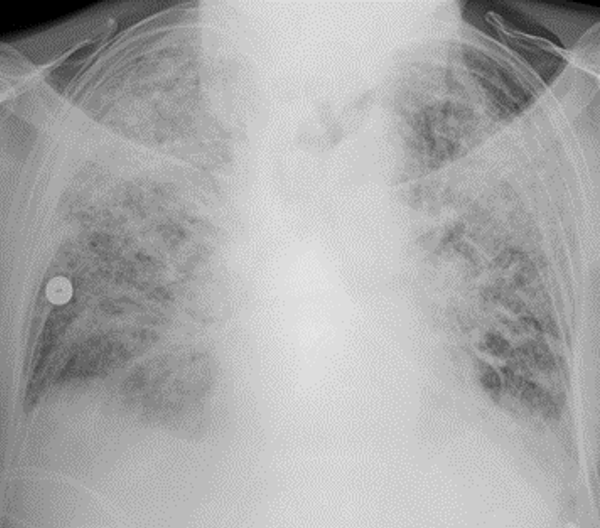

Schocklunge oder ARDS

Es hat sich gezeigt, dass wenn Patienten mit COVID-19 ernsthaft erkranken, dies meist in der zweiten Woche der Infektion geschieht. Das Fieber steigt progressiv an und oft kommt es zu einer schweren Entzündungsreaktion in der Lunge, die als hyperinflammatorische Schocklunge oder ARDS - acute respiratory distress syndrome - bezeichnet wird. In diesem Fall werden die Alveolen, in denen der Gasaustausch stattfindet, undicht und die Atmung wird ernsthaft beeinträchtigt. Die Atmung ist oft notwendig und die Organe können aufgrund von Sauerstoffmangel versagen.